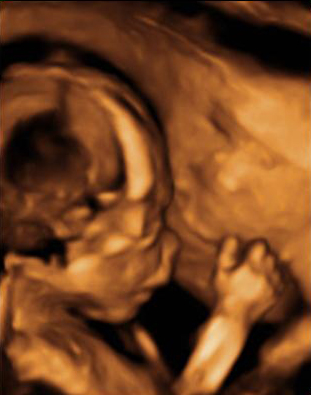

Ecografía semana 20: Cara de perfil y mano del bebé

En la semana 20 de embarazo el bebé aún se mueve libremente dentro del útero materno. Como este feto con la cara de perfil, que se apoya en la pared uterina ayudándose del puño y la nariz. Podemos ver perfectamente la mano cerrada y los dedos, así como los rasgos del perfil y el cráneo.

Cara fetal de perfil y mano frente a la pared del útero

En esta imagen podemos ver cómo el bebé aún tiene sitio para moverse a sus anchas en el útero durante la semana 20 de gestación.